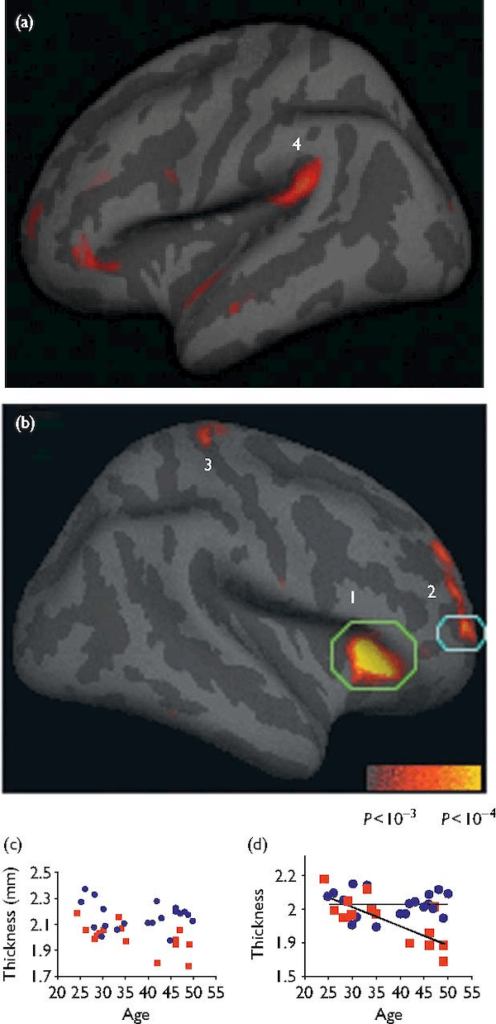

… while also increasing the quality of life. It was then that Lazar decided to do a little neuroscience research of her own. Her first study took a close-up look at people who had engaged in mindfulness for 7 to 9 years vs. a control group. Individuals with a strong background in mindfulness meditation had a higher level of gray matter in several areas of their brains, including the auditory and sensory cortex, and insula and sensory regions. This gray matter plays a prominent role in how we:

But there was another factor in the study's results that caught Lazar's attention: Individuals regularly involved in practicing mindfulness had more gray matter in the frontal cortex of their brains — the area linked to decision-making and working memory.

Why is this noteworthy? Most people experience a shrinking of the cortex as they age, but Lazar found that 50-year-olds who engaged in meditation displayed the same amount of gray matter as individuals who were half their age.

Fig. 1 Cortical regions thicker in meditators than in controls. (a and b) Statistical map depicting between-group differences in thickness at each point on the cortical surface overlaid on the inflated average brain. All points meeting a P < 0.01 threshold (uncorrected) are displayed to better illustrate the anatomic extent of the areas and the relative specificity of the findings. Numbered regions: (1) insula, (2) Brodmann area (BA) 9/10, (3) somatosensory cortex, (4) auditory cortex. (c and d) Scatter plot of mean cortical thickness of each participant in the subregion above threshold within each circled region of (c) insula and (d) BA 9/10, plotted versus age. Meditation participants: blue circles, control participants: red squares. https://www.ncbi.nlm.nih.gov/pmc/articles/PMC1361002/

To be sure that this was not because some individuals had more gray matter from the start, Lazar and her team conducted a second study. This time, they invited individuals who had no experience in meditation to join an eight-week mindfulness training program.

The results were remarkable. The team discovered that a mere eight weeks of mindfulness meditation changed people's brains for the better. Participants experienced a thickening in several regions of the brain, including the:

- TPJ, which is involved in empathy and the ability to take multiple perspectives

- Left hippocampus, which is involved in learning, memory, and emotional regulation; and the

- Pons, a part of the brain stem where regulatory neurotransmitters are generated

They also experienced shrinkage of the amygdala, the region of the brain that is associated with fear, anxiety, and aggression. This reduction in the overall size of the amygdala directly correlated to a reduction in the stress levels of those individuals.